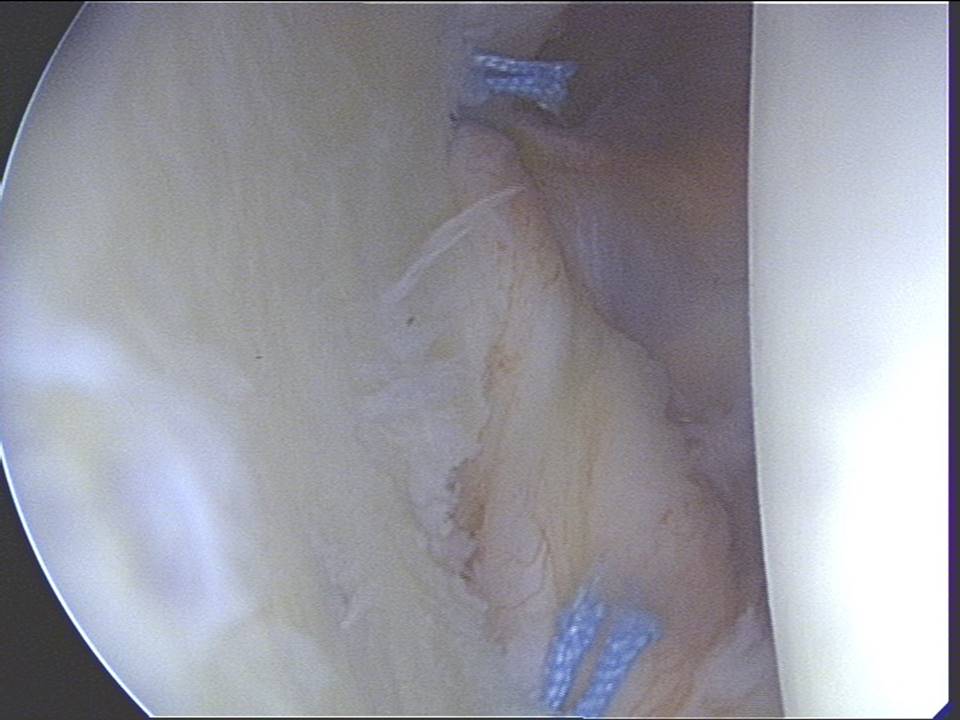

Gelenkspiegelungsbild einer abgelösten Gelenkkapsel am vorderen Pfannenrand der Schulter

5. Operationsergebnis mit liegenden Fäden nach Befestigung der vorderen Labrum-Kapsel-Bandapparat eines Schultergelenkes bei vordere Schulterluxation